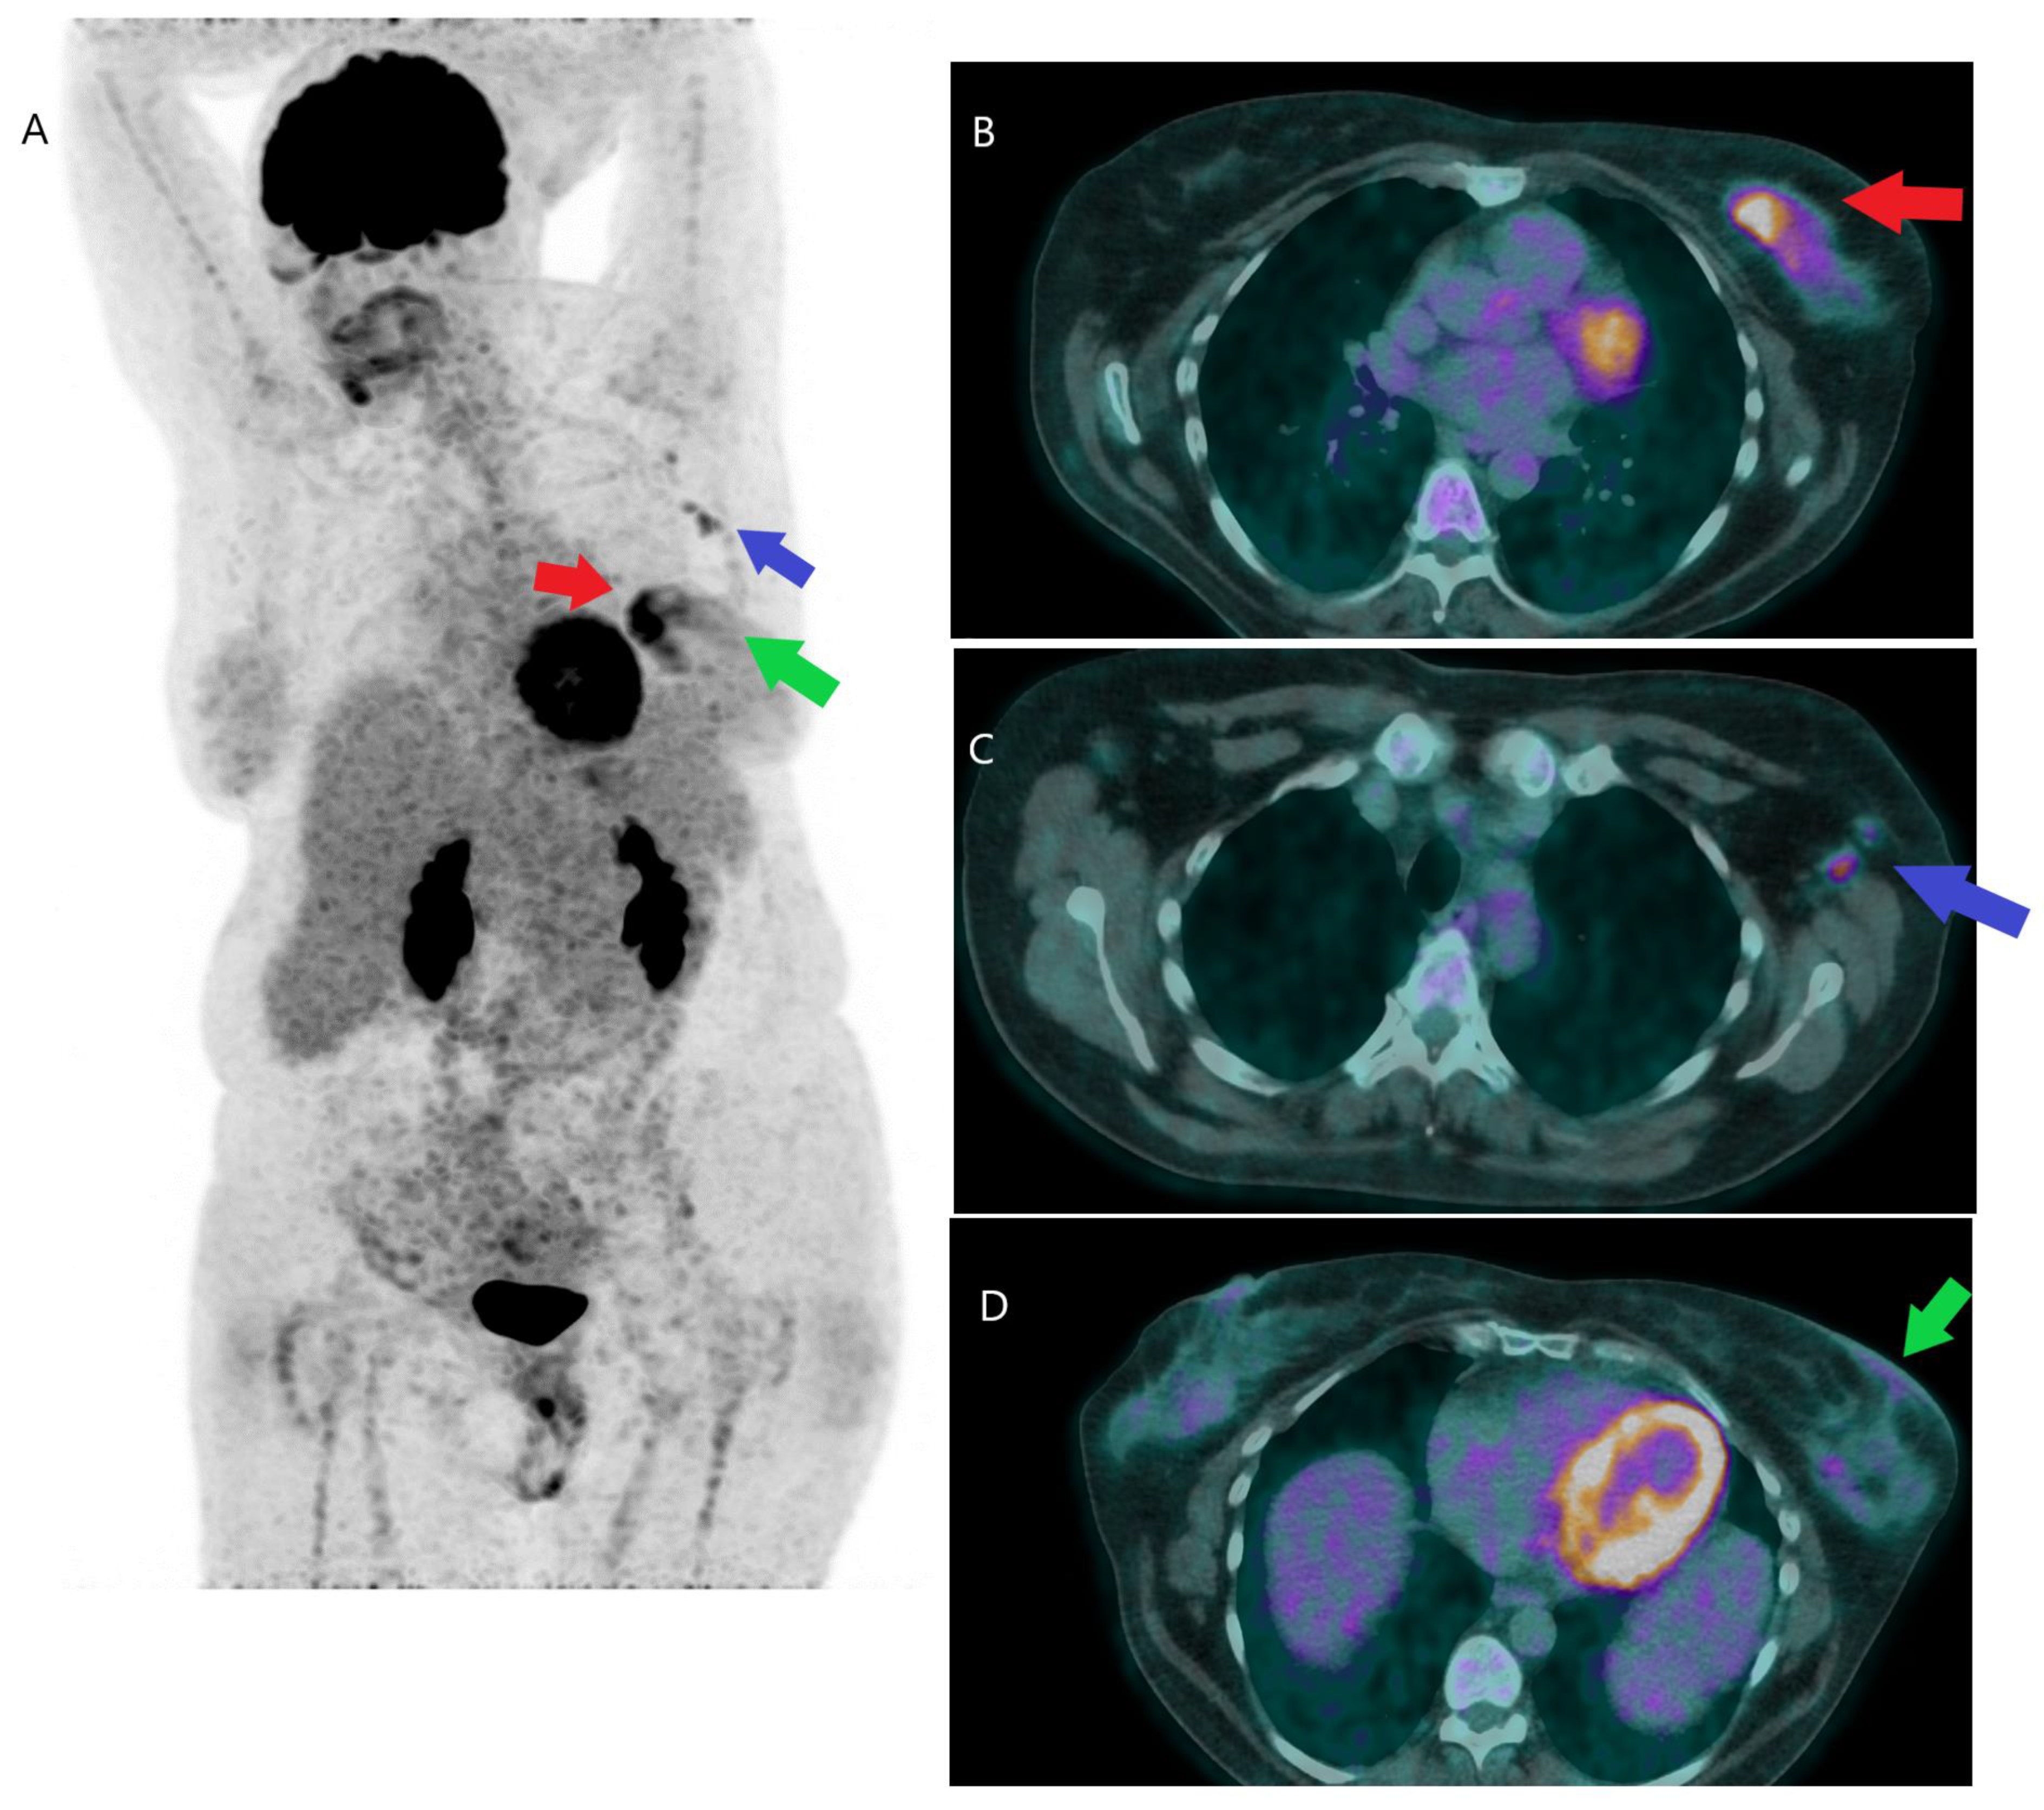

PSMA PET-CT Accurately Detects Prostate Cancer Spread - NCI PET Scan: What It Is, Types, Purpose, Procedure & Results PET/MRI biomarkers guide personalized treatment for patients with pancreatic cancer - Mayo Clinic News Network PSMA-PET is rapidly changing the standard of care for prostate cancer patients | Pet Scan Cancer